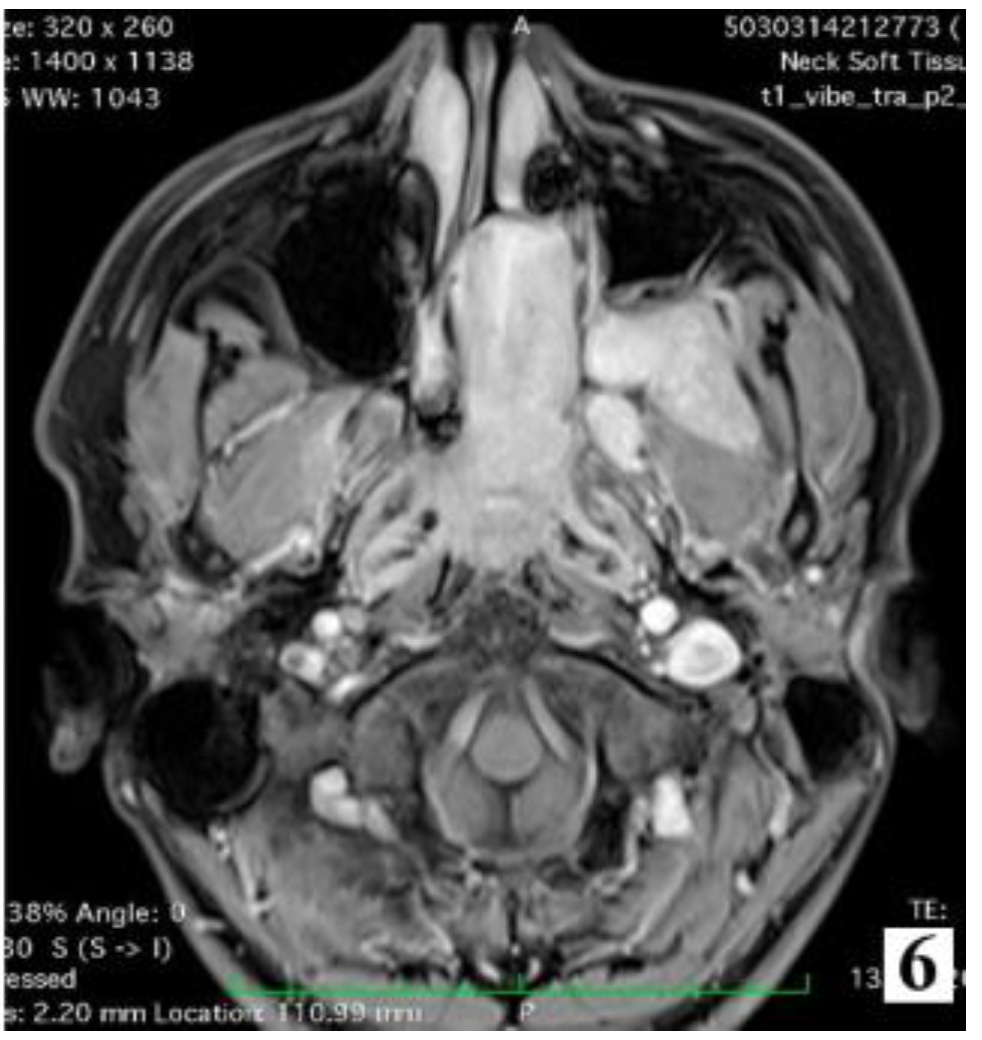

Computer tomograph imaging studies are the ideal investigation when assessing bone involvement, able to identify options for surgical treatment. A pathognomonic sign is the Holman-Miller sign describing the anterior bowing of the posterior maxillary wall in cases with sphenopalatine fossa invasion [6].

Management of stage IIC cases, with extension into the infratemporal fossa or extension posteriorly to the pterygoid plates, can be done by transnasal approach alone or by a combined approach. Preoperative embolization is mandatory for identifying the vascular feeding source and reducing intraoperative bleeding.

Figure 8. Preoperative MRI of a stage IIC juvenile angiofibroma. The Holman-Miller sign (the anterior bowing of the posterior maxillary wall) on the CT scan (part 2).